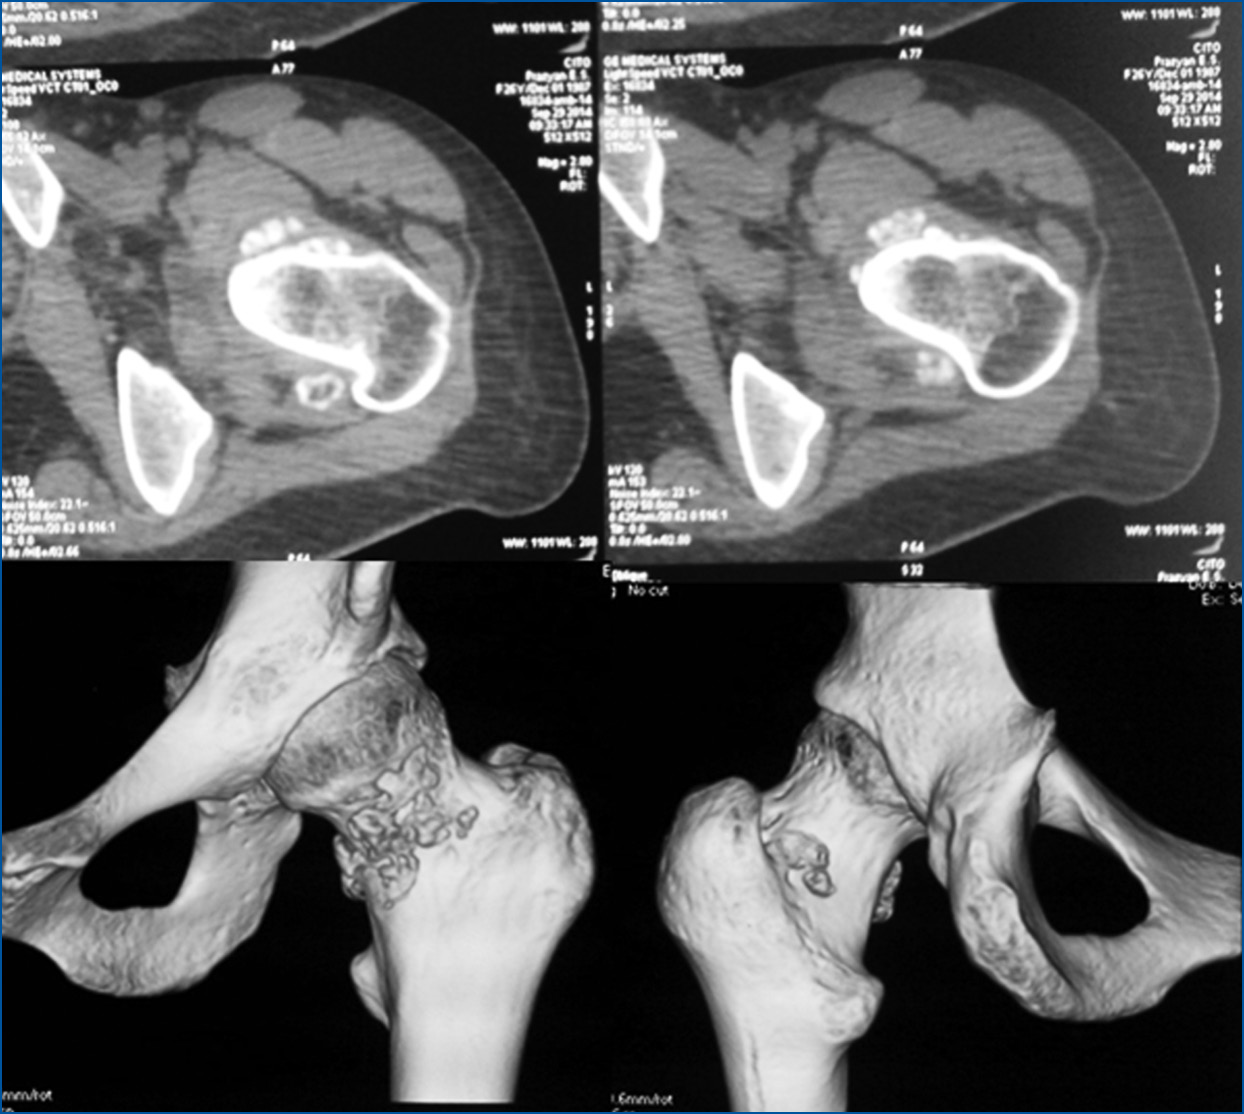

Перед операцией у всех пациентов были проведены сбор жалоб и анамнеза, физический осмотр с целью оценки функционального состояния суставов и их подвижности, а также магнитно-резонансная томография (МРТ) для визуализации внутрисуставных изменений (рис. 1, 2).

Рис. 2. Пациентка Р., хондроматоз тазобедренного сустава: результаты компьютерной томографии.

Fig. 2. Patient R., synovial chondromatosis of the hip: computed tomography findings.